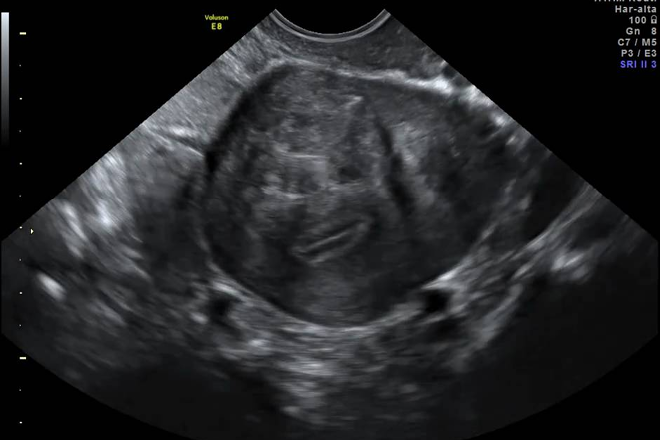

Esta es la alteración más común encontrada en la práctica diaria de la ultrasonografía en el ámbito de la patología uterina. Se caracteriza por el aumento de las dimensiones del útero, pérdida de la homogeneidad de la ecogenicidad uterina y en ocasiones, la ondulación del contorno uterino.

Los miomas intramurales o miometriales son los más frecuentes y son los responsables principales del crecimiento uterino, aumentando inicialmente el diámetro anteroposterior del útero y dándole una forma esferoidal. La presencia de miomas subserosos puede llevar a un contorno ondulado del útero. Estos miomas pueden ser sésiles o pediculados, simulando tumores anexiales no relacionados con el útero.